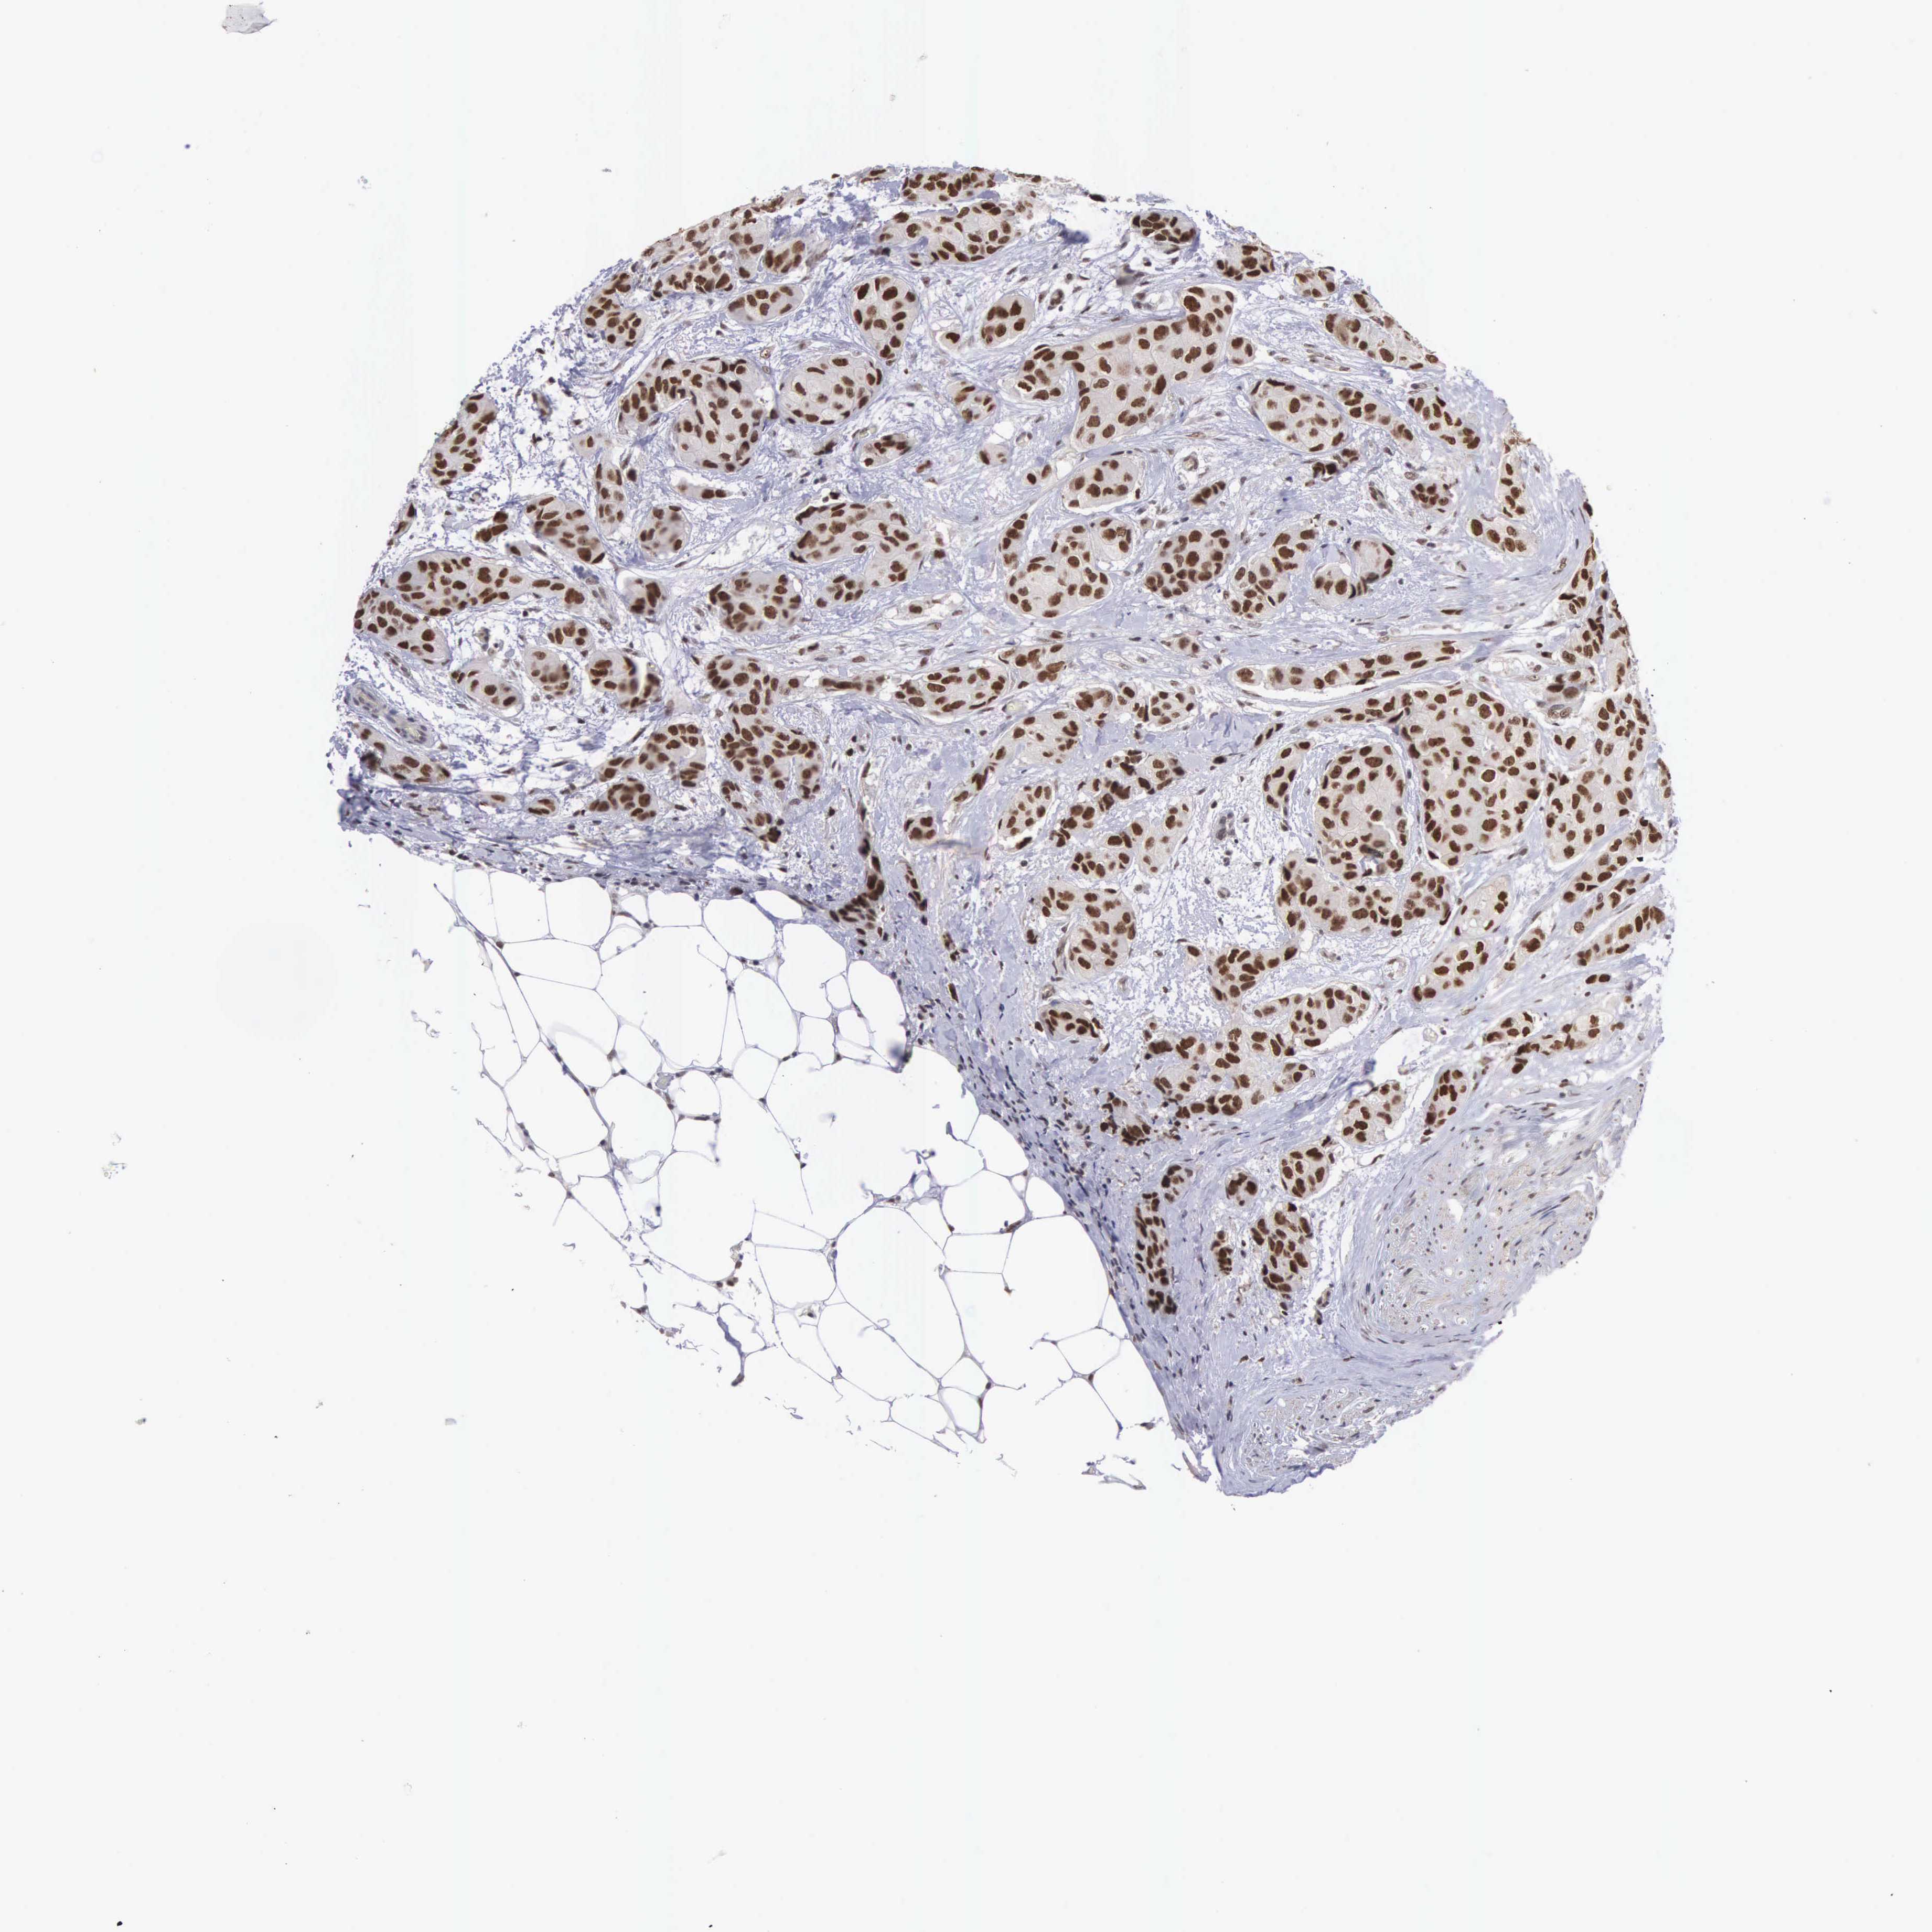

BRCA TCGA BRCA VALIDATION PROTEIN EXPRESSION

Breast cancer

Human cancer